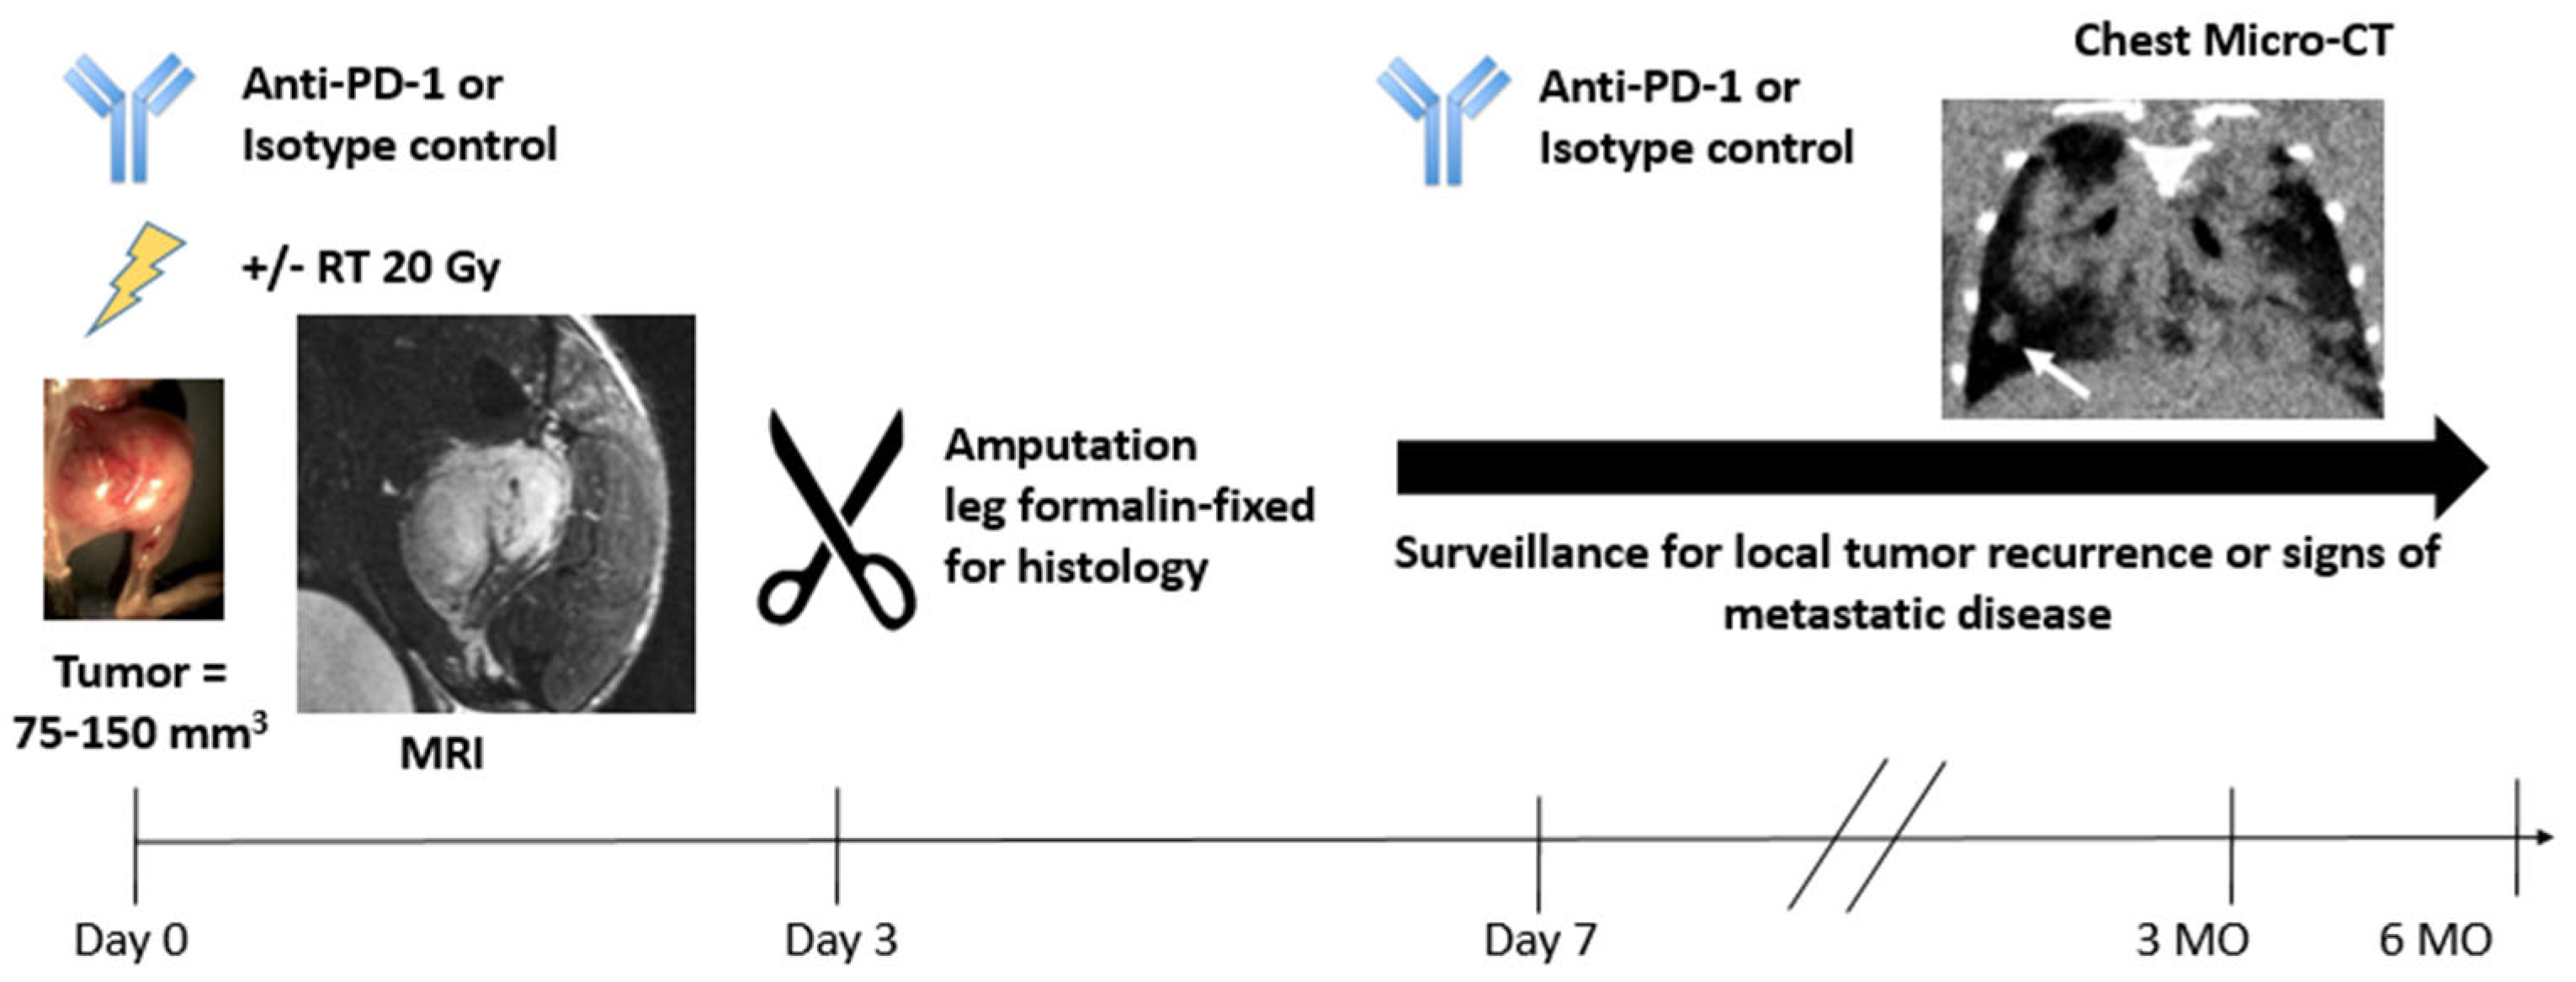

2.2. The Duke Preclinical Research Resources for Quantitative Imaging Biomarkers